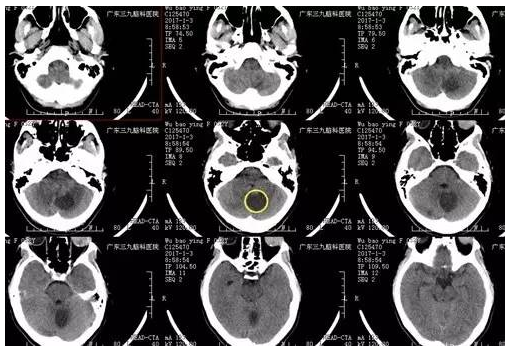

伍某某,32岁,发现颅内占位病变2年,行走不稳1天,为求进一步治疗,来我院就诊。入院后完善相关检查后,术前CTA提示实体病变,血供异常丰富,术前MR提示肿瘤位于桥臂背侧,行小脑血管母细胞瘤切除术,手术由神经外一科主任张良主刀完成,术程顺利,术后病变全切除,术后病理提示血管母细胞瘤(WHO I级),目前恢复良好。

▲术前CT